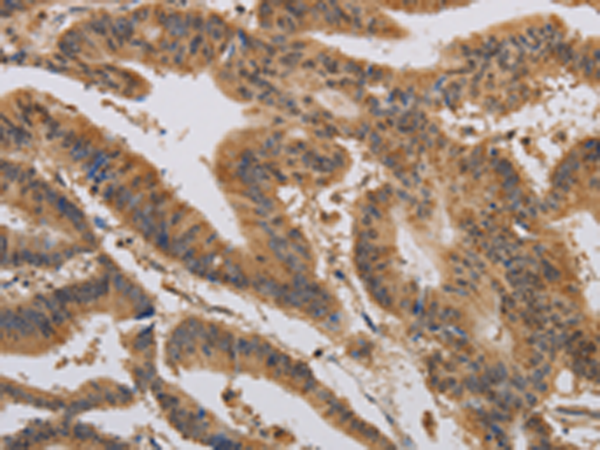

分类: 科研抗体货号: P10632别名: MCH4, ALPS2, FLICE2应用: WB,IHC反应种属: Human